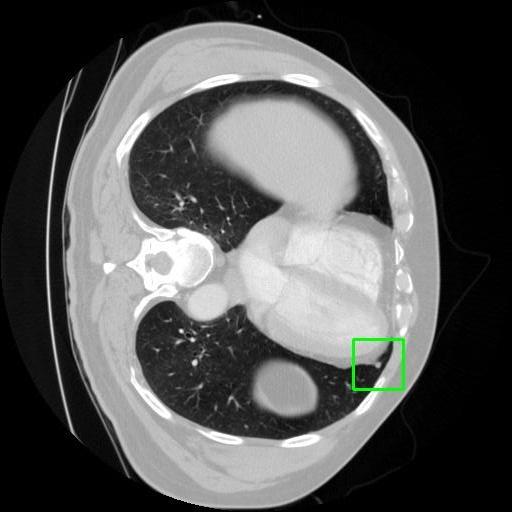

We developed an AI-based system using deep learning models for analyzing lung CT scans to detect and classify pulmonary nodules. We chose the YOLOv11 architecture for its enhanced object detection capability and adapted it specifically for medical imaging, incorporating pixel-level precision and severity classification.

Classification into three severity levels with colored bounding boxes.

Designed a severity classification system that categorizes nodules into null, moderate, and severe using colored bounding boxes, assisting in rapid clinical decision-making.